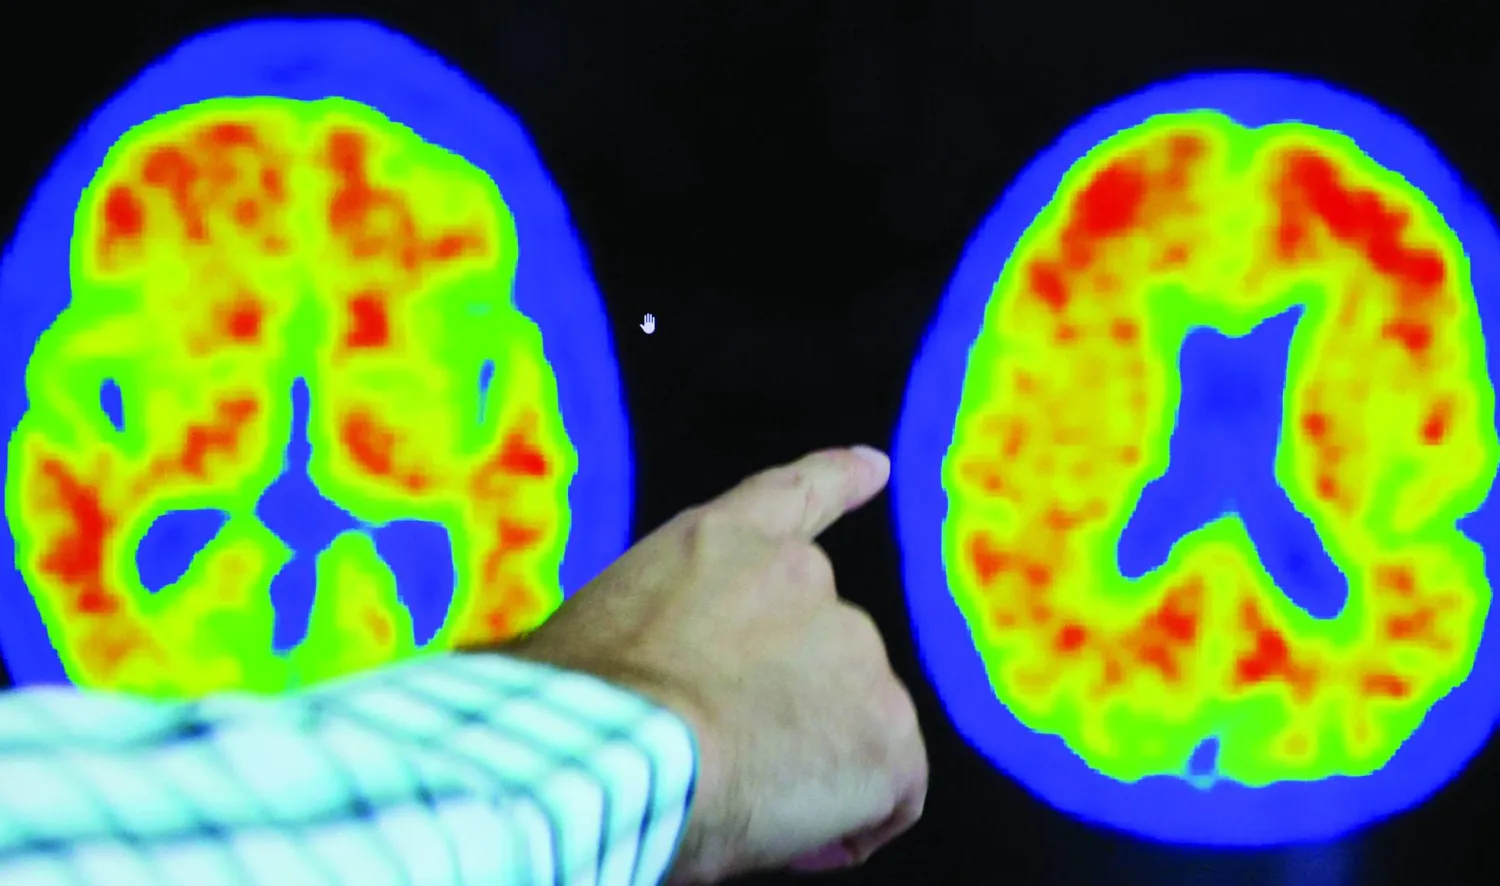

ومرض ألزهايمر هو مرض عصبي تنكسي يؤدي إلى التدهور التدريجي للوظائف المعرفية، مثل الذاكرة، واللغة، والتفكير، والسلوك، والقدرات على حل المشكلات. وهو السبب الأكثر شيوعاً للخرف، حيث يمثل 60 - 80 في المائة من الحالات.